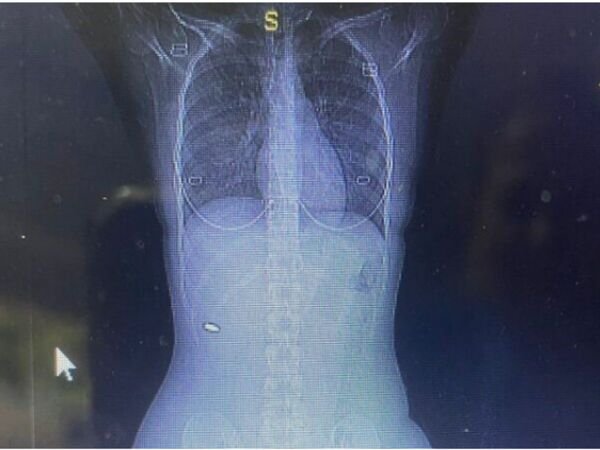

जानकारी के मुताबिक, महिला का नाम अदि ब्लॉय है और वह वेस्ट बैंक में रहती हैं। महिला ने बताया कि विगत तीन महीने से रीढ़ की हड्डी में दर्द था। अदि को शक हुआ कि सोने के दौरान नस खींच गई होगी। लिहाजा, दर्द को कम करने के लिए वह अक्सर पेन किलर ले लेती थी। लेकिन, कुछ दिनों से दर्द बर्दाश्त नहीं हो रहा था। मजबूरन वह डॉक्टर के पास पहुंच गई। डॉक्टर्स को भी शुरु में समझ नहीं आया, लेकिन जब सिटी स्कैन किया तो सब चौंक गए। क्योंकि, रीढ की हड्डी में एक बुलेट फंसी थी। इसके बाद डॉक्टर्स ने बिना देरी किए उसकी सर्जरी की और 5.56mm की एक बुलेट निकाली। डॉक्टर्स का कहना है कि यह किसी चमत्कार से कम नहीं है। क्योंकि, उसकी जान भी जा सकती थी।

इधर, महिला का कहना है कि उसे बिल्कुल ही अंदाजा नहीं था कि रीढ़ की हड्डी में बुलेट है। महिला ने बताया कि तीन महीने पहले वो एक दोस्त की शादी में गई थी। वहां उसे कमर में दर्द हुआ। अदि को लगा कि नस खींच गई होगी। उसने पीछे जब हाथ लगाकर देखा तो हाथ में खून लगे थे। महिला को लगा कि कोई खरोंच लगा है, जिसके कारण खून बह रहा है। उसे बुलेट लगी है इसका अंदाजा बिल्कुल ही नहीं था। लेकिन, इस खुलासे से हड़कंप मच गया है। इधर, पुलिस भी सच्चाई ढूंढने में जुट गई है।